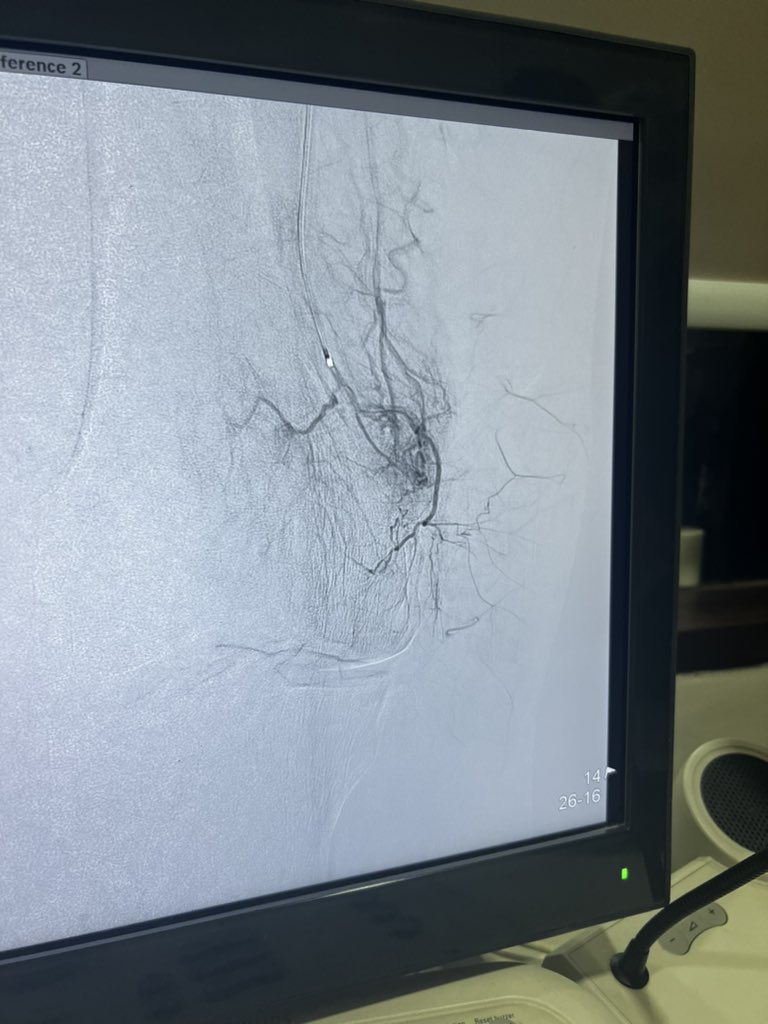

#uterine #fibroid embolisation. Symptomatic improvement with 50 % volume reduction in 4 months. 7.5 cms to 3.7 cms. #SHNB Keith Pereira MD, #VIrad sir for the emphasis on SHNB, makes difference on post procedure care.

#uterine #fibroid  embolisation. Symptomatic improvement with 50 % volume reduction in 4 months. 7.5 cms to 3.7 cms. #SHNB <a href="/keithppereira/">Keith Pereira MD, #VIrad</a> sir for the emphasis on SHNB, makes difference on post procedure care.